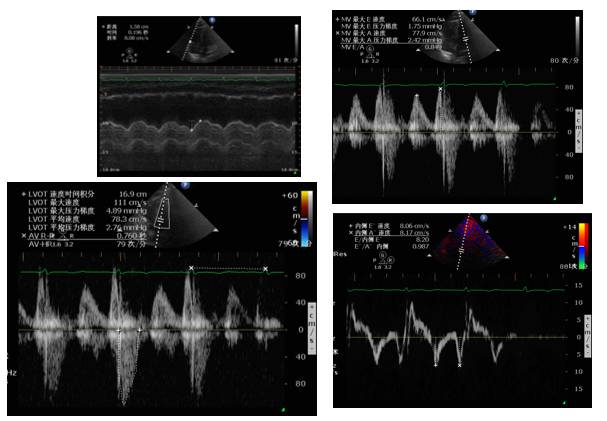

心脏彩超

右:左=1:1

IVC>2.5cm

EF:0.35

♥床边心超提示:心率增快时左心收缩力明显减弱,伴充盈压高,予以艾司洛尔(0.05mg/kg/min)控制心室率后心率降至55左右,血压明显改善,102/70mmHg,复查心超左心收缩舒张功能均改善。